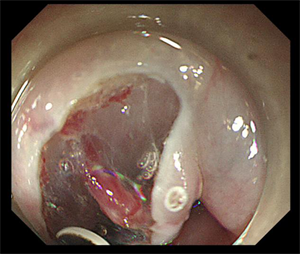

术前,消化内科与呼吸与危重医学科、心血管内科、ICU、麻醉科对病例进行了充分讨论,经过精心的术前准备,在麻醉科和内镜护理团队保驾护航下,顺利完成食管早癌内镜手术。术后,呼吸与危重医学科和心血管内科协助治疗,经病理科对标本的诊断,提示患者食管早癌已治愈性切除,后期无需放疗、化疗,定期复查胃镜及胸腹部CT即可。

是通过内镜前端针对粘膜、病灶周围进行注射,在胃镜下对病变粘膜进行切割剥离,通过剥离使病灶离开胃壁或者是粘膜层。ESD术具有创伤小、不改变消化道结构、避免外科手术风险、提高术后生活质量等优点,可以帮助早期肿瘤病人达到治愈的目的。